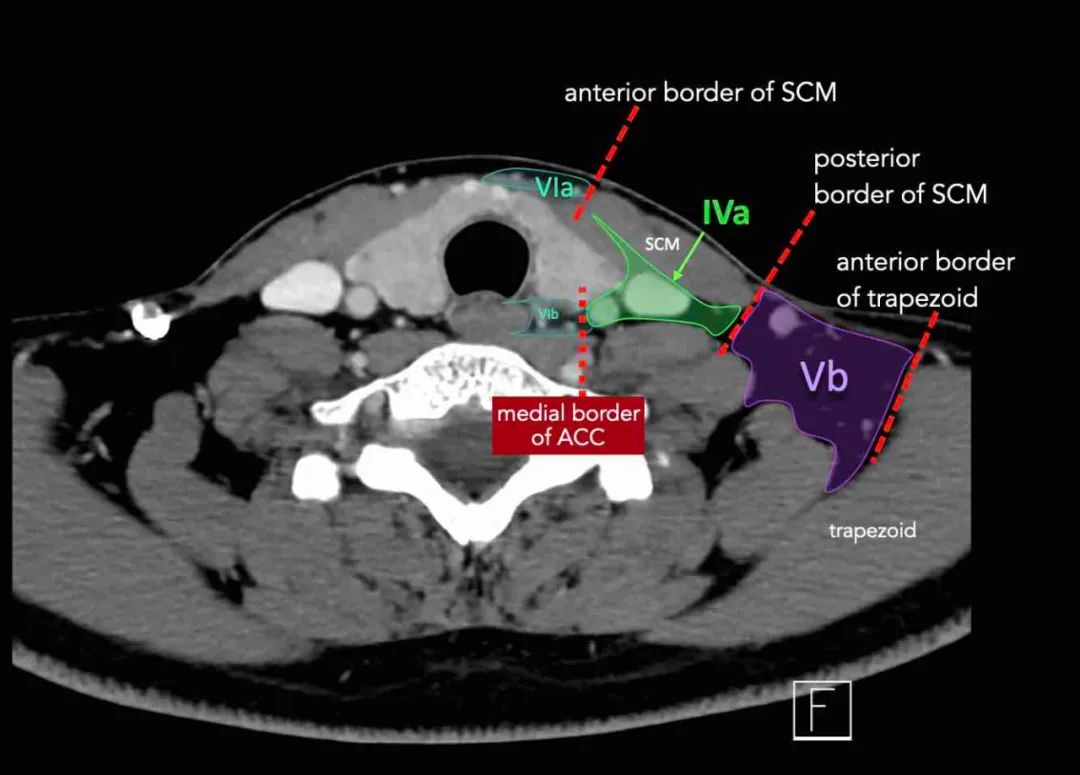

IVa和IVb水平之间的边界设置在距胸锁关节2 cm的颅侧。

IVa级

这些淋巴结有隐藏来自下咽癌、喉癌、甲状腺癌和颈段食道癌的转移的风险。

IVb级

这些淋巴结有隐藏来自下咽部、声门下喉、气管、甲状腺和颈段食管的癌症转移的风险。

第五层包含位于胸锁乳突肌后面,围绕着副神经和颈横血管的下部。